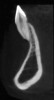

Fig 5. CBCT sagittal view of the same patient showing thin/no bone on the lingual aspect.

Figure 5